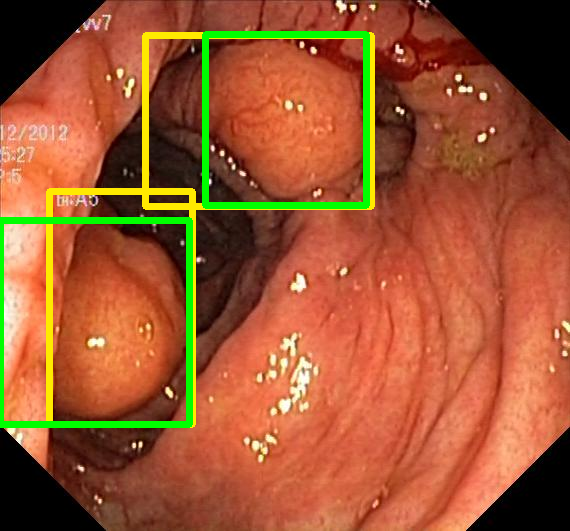

We evaluate the resulting object detection models using the test data, which is pre-processed in the same manner as the validation data, with AP@[.5:.95] (AP for conciseness), AP@.5 (AP50), and AP@.75 (AP75) computed for predicted bounded boxes with a confidence score \geq0.05. For all metrics, a higher value indicates better performance. The results are presented in Table VI, and some examples for predicted bounding boxes with a confidence score \geq0.5 are shown in Fig. 1.

Figure 1: Targets (yellow bounding boxes) and predictions (green bounding boxes) for two randomly selected instances of the Kvasir-SEG test set. For conciseness, we denote ResNet50s with RN, ViT-Bs with VT, Hyperkvasir-unlabelled with HK, ImageNet-1k with IN, MoCo v3 with MC, Barlow Twins with BT, MAE with MA, supervised pretraining with SL, and no pretraining with NA-NA.